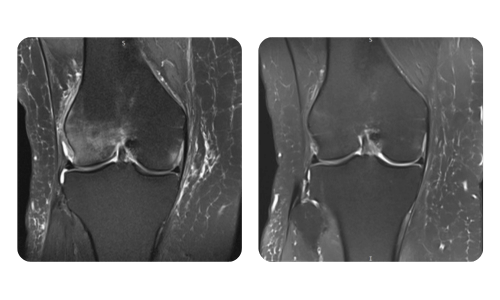

Der Fortschritt unserer Patienten, gemessen vor und nach der hyperbaren Therapie, spiegelt die Effizienz und die positive Wirkung der Behandlung wider. Entdecken Sie dokumentierte Ergebnisse der hyperbaren Therapie in der Klinik Hyperbarium Oradea, basierend auf klinischen Bewertungen und objektiven Daten, die signifikante Verbesserungen bei verschiedenen Erkrankungen belegen.